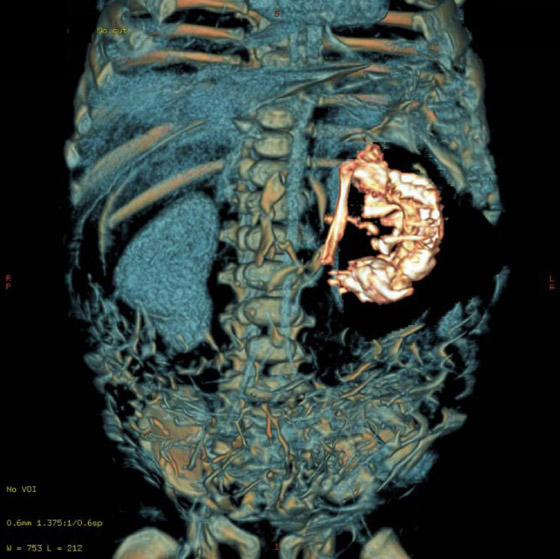

4- جنين داخل جنين:

أحيانًا يستطيع توأم مغاير خارجي التواجد بشكل كامل داخل توأمه الذي يكون سليمًا، وهو ما يعرف باسم "الجنين داخل الجنين" أو Fetus in Fetu. هي ظاهرة نادرة للغاية، حيث لم يتم توثيق أكثر من 200 حالة عبر التاريخ، وعادة ما يكون هنالك جنين واحد داخل الجنين، لكن في إحدى الحالات وجد الأطباء 11 جنينًا داخل جنين.

إنها ظاهرة طاف حولها جدل كبير بين الباحثين والعلماء حول الطريقة التي تحدث بها، كما أن بعضهم لا يتفق حتى على أن "الجنين" الداخلي يعتبر توأمًا أساسًا، حيث يعتقد هؤلاء أن ظاهرة "الجنين داخل الجنين" ما هي إلا حالة ورم مسخي متطور، الذي هو عبارة عن ورم يتكون من عدة أنواع من أنسجة الجسم.

كما يوجد فريق آخر من الباحثين الذين يعتقدون بأن الظاهرة تحدث بسبب وقوع خلل أثناء تطور الجنين، حيث تنقسم بعض الخلايا الجذعية التي من المفترض أن تتطور لتصبح أعضاءً أخرى بشكل غريب. لكن آخرين يقولون بأنه توأم حقيقي، ذلك أن الجنين داخل الجنين يملك عمودا فقريًا، وغالبا ما تتطور لديه أعضاء مثل أطراف الجسم.

بالطبع قد يكون أي من الآراء والنظريات السابقة صحيحًا، حيث قد تكون هنالك الكثير من الطرائق المختلفة التي تنتهي بجنين متطور بشكل جزئي داخل جنين آخر متطور بشكل كامل. قد يعني هذا أن دراسة هذا النوع من التوائم قد يساعد الأطباء على فهم كيف أن بعض الأورام الجنينية تصبح مصدر إشكال بينما تبقى أورام أخرى حميدة، كما قد تساعدنا على فهم بعض الأمور المثيرة حول البرمجة التطورية للخلايا.

قد يكون حدوث ظاهرة الجنين داخل جنين راجعًا لكون أحد الجنينين يحتوي الآخر في مرحلة ما من تطورهما، أي أن الظاهرة أقرب إلى فكرة الالتحام لكنها أكثر تطرفًا. وهو ما لا يعتبر بعيد المنال مثلما قد يبدو عليه، لأنه توجد حالات موثقة لأجنة توأم يمتص أحدها جزءا من الآخر أو يمتصه ويحتويه بشكل كامل.